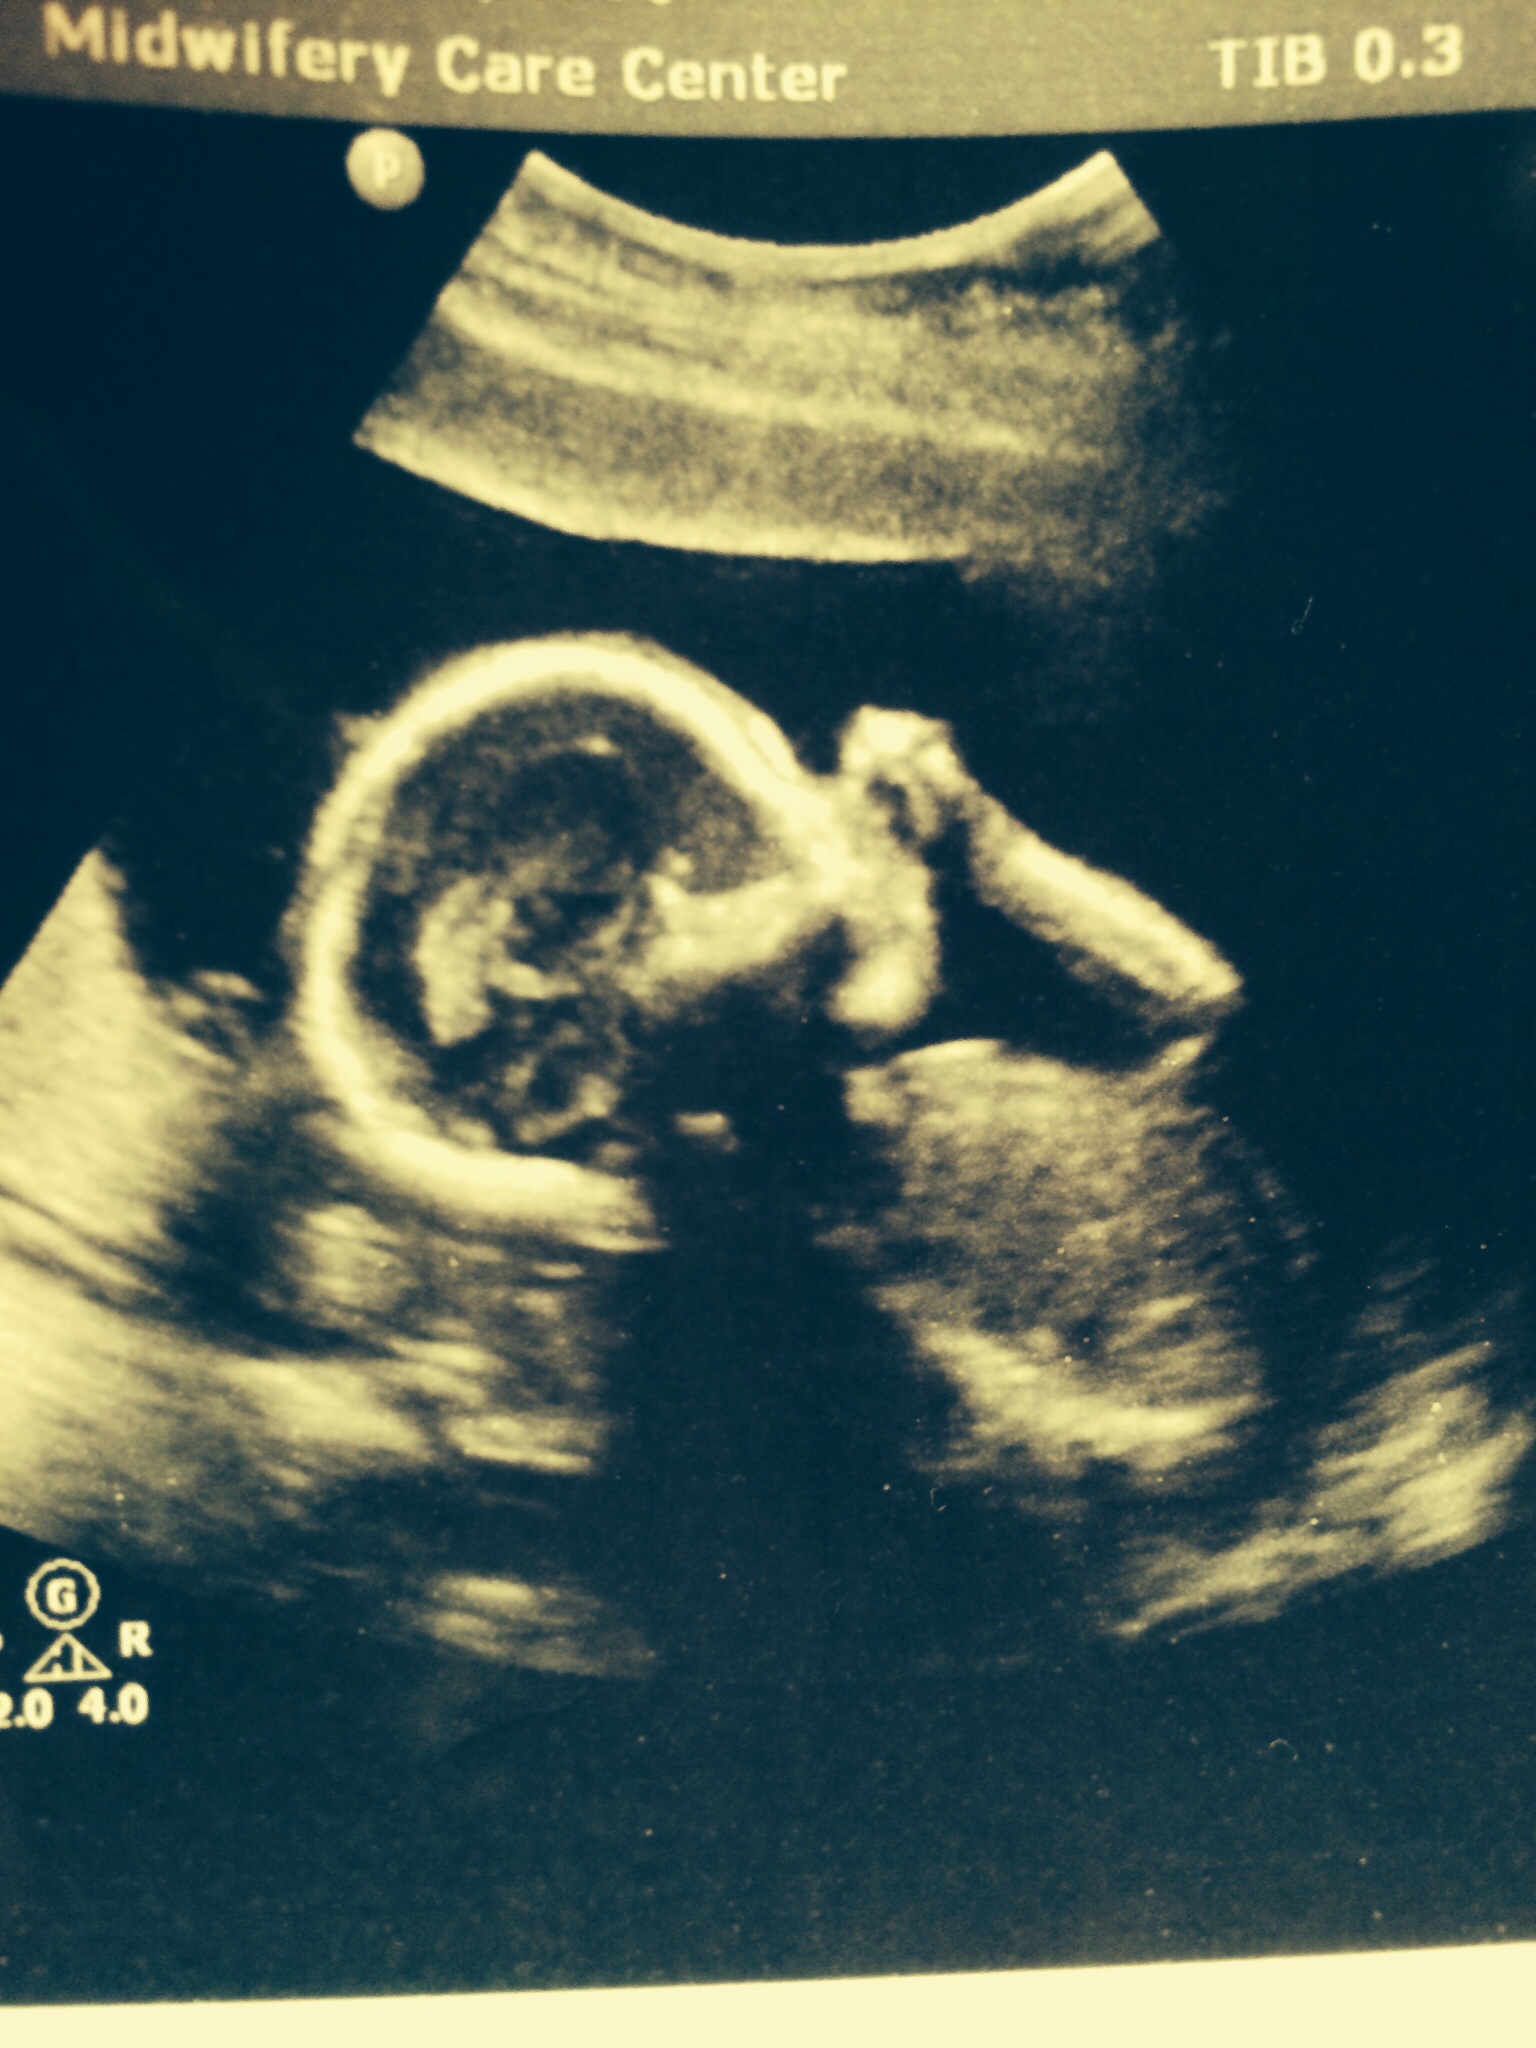

Eta: my baby sucking it's thumb. Couldn't get a crotch shot, but at least I know he or she is still okay. Hope pic isn't huge. Uploading from phone. This is beautiful.

• I am so sorry you are going through this, I hope you feel better soon. That pic of your baby is perfect

And that is a beautiful baby picture! I'm glad he/she is OK!

• I'm really sorry that you are going through this. I hope you get well soon and find a solution. Your little one is beyond adorable. I'm glad he or she is okay.